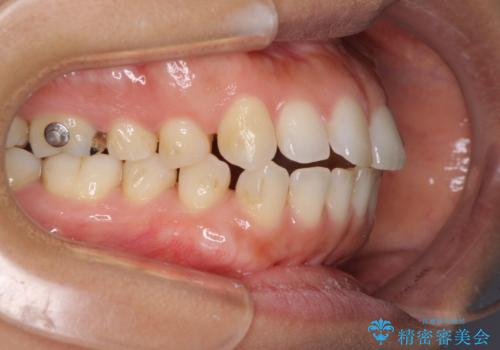

受け口傾向の前歯 すきっ歯の改善

- 前歯の隙間と口元の突出感を気にして来院された患者様です。

嚥下時に舌を突出させる癖があり、成長期に下顎が有意に成長し、歯と歯の間に隙間ができてしまいました。

舌の癖を改善し、インビザラインにて治療を行うこととしました。

舌癖を改善したことで、隙間や突出感を改善することができました。

隙間は後戻りしやすいため、舌側を細いワイヤーで固定することとしました。